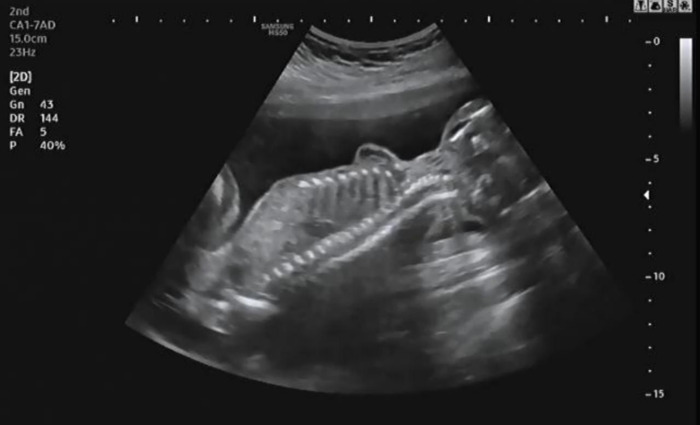

세밀하게 장기를 확인하고 태아의 척추와 갈비뼈들이 잘 형성되고 있는지 확인했다. 21주에는 일반적으로 태아의 머리 엉덩 길이(CRL)가 16~18cm인데 작은 크기임에도 내 품에서 생명이 싹트고 있음을 다시 깨닫게 되었다.